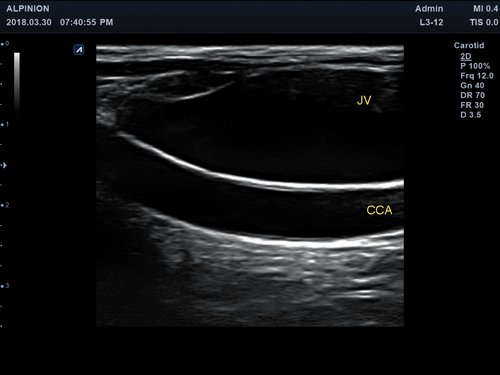

Anwendungsbereiche Abdomen MSK, Nerven, Karotis, periphere Gefäße, Schilddrüse, Mamma

• B-Modus: Darstellung zweidimensionale Bilder anatomischer Strukturen